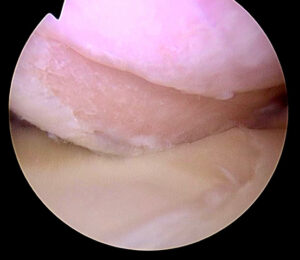

En una entrada anterior del blog hablábamos acerca de la inestabilidad de hombro, sus aspectos generales, y cómo era importante identificar si había un defecto de hueso asociado. En estas

El hombro es la articulación más móvil del cuerpo. Debido a su peculiar anatomía, en la que la superficie articular de la glenoides es mucho más pequeña que la cabeza